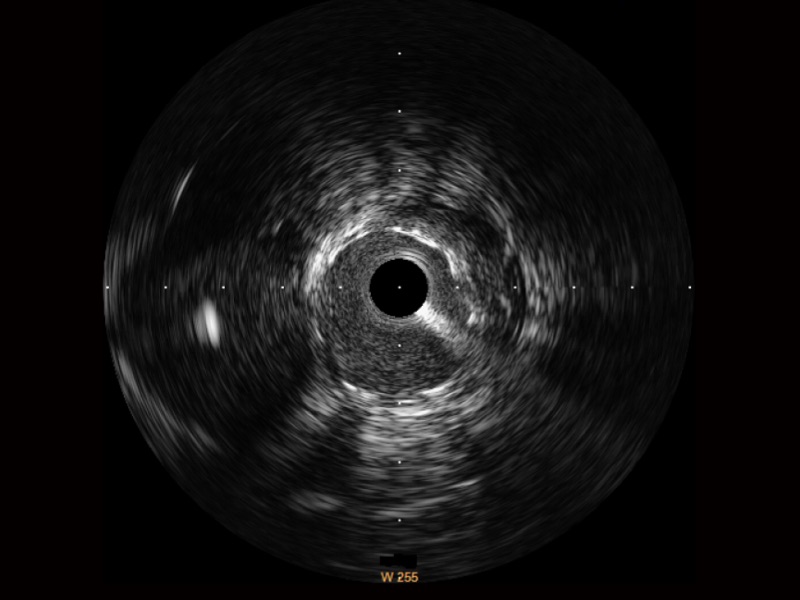

球速体育入口宽频IVUS图像

传统IVUS图像

对比传统IVUS导管成像,球速体育入口宽频IVUS图像的近场支架梁显影更细腻,远场中膜外血管仍清晰可辨,兼顾远中近,兼顾分辨力与穿透深度